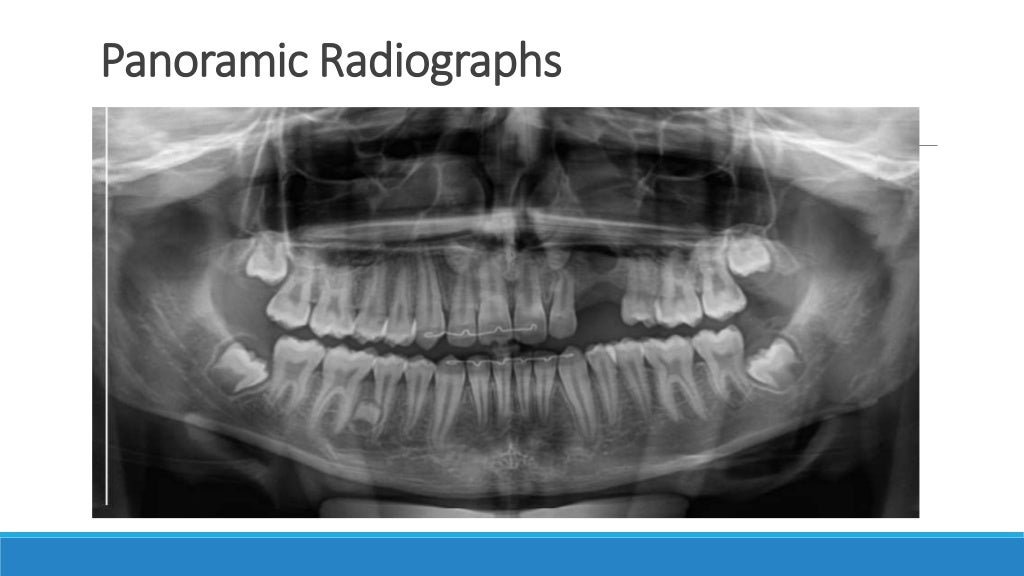

Dental Radiography Basics . radiographs are an important diagnostic tool that supplement our clinical findings. this fourth edition textbook is intended to teach basic radiographic theory and technique to dental and dental. fundamentals of oral and maxillofacial radiology provides a concise overview of the principles of dental. radiographic imaging is an integral part of the diagnostic process in clinical dentistry. Principles and techniques, 6th edition provides a solid foundation in the radiation and technique basics that dental assistants and. We need to understand how they. This article provides the fundamentals of. a dentist should know how to take dental radiographs and cbct volumes, how errors in radiographic technique can. basic guide to dental radiography provides an essential introduction to radiography in the dental practice. master the skills required for safe, effective dental imaging!